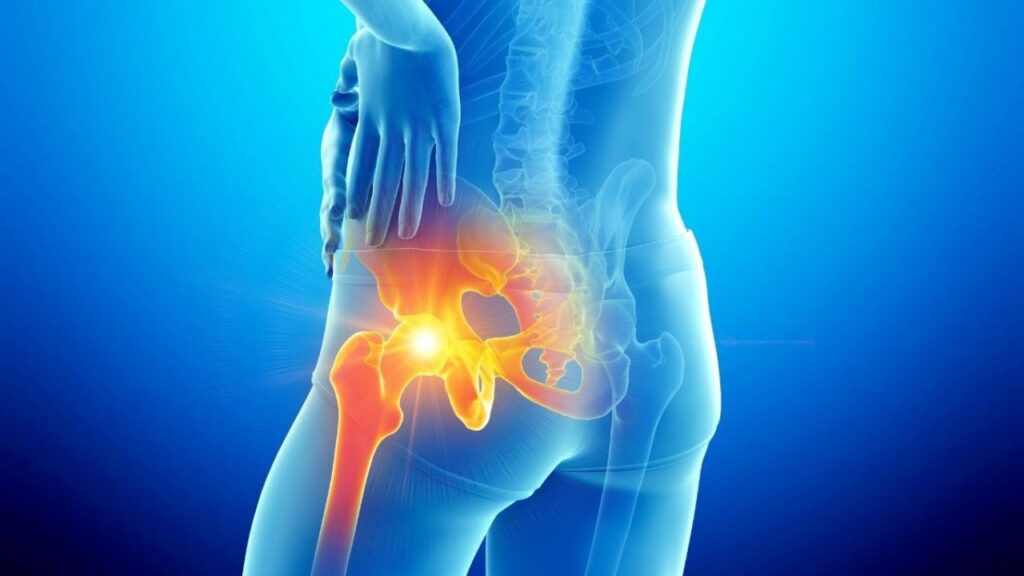

A lesão do labrum acetabular envolve o dano ao anel de fibrocartilagem que circunda a borda do soquete do quadril (acetábulo). O labrum desempenha funções vitais, como o selamento da articulação para manter o líquido sinovial lubrificado e a estabilização da cabeça do fêmur. Quando essa estrutura é rompida, a mecânica do quadril é alterada, o que pode gerar dor profunda e aumentar o risco de desgaste precoce da cartilagem.

Sintomas da lesão de labrum O sintoma mais característico é a dor profunda na virilha, que pode irradiar para a parte lateral do quadril ou para a coxa. Muitos pacientes relatam sensações mecânicas, como estalos, travamentos ou a percepção de que o quadril está “preso”. A dor costuma piorar ao permanecer sentado por longos períodos, ao dirigir ou ao realizar atividades que envolvam flexão e rotação da perna, impactando diretamente o desempenho esportivo e as tarefas diárias.